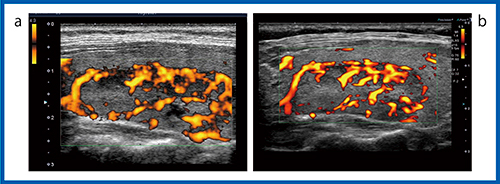

2.高分解能モードの機種による進化

東芝メディカルシステムズのAplioシリーズでは,高分解能の血流表示方法として,高分解能,高フレームレート,低ブルーミングで微細な血流を描出するAdvanced Dynamic Flow(ADF)に加え,低流速の微細な血流を描出するSMIが使用できる。これらについても装置間で比較した画像を供覧する。

1)Advanced Dynamic Flow:ADF

図7は,正常な甲状腺のADFだが,Aplio i800(a)では細かい血流まで描出され,血管走行を追うことができる。甲状腺腫瘍でも,Aplio 500やAplio i800では腫瘍内部の微細な血管の様子が観察できる。

図7 超音波診断装置の進化:ADF(12MHz)

a:Aplio i800 b:Aplio XG c:Aplio 500

2)Superb Micro-vascular Imaging:SMI

より低速な血流を描出できるSMIでは,装置の性能が向上することで血管の描出能の違いがより明確にわかる。図8は,color-coded SMI(cSMI)でカラー表示された血流の画像だが,Aplio i800(b)では通常の血流に加えて,腫瘍の内部まで入り込むような微細な血管の様子まで確認することができる。また,血流信号をモノクロで表示したmonochrome SMI(mSMI,図9)の場合,Aplio i800(b)では濾胞構造を示す腫瘍の周囲の血管構造まで確認できるほど低流速の血流が描出されている。

濾胞性腫瘍の血管構築は,良性では類円形の血管走行できれいな濾胞を描いているが,癌腫ではイレギュラーに網目状に発達した構造を示す。癌腫は進行するにしたがって主要血管網の中心を貫通する血管が認められ,カラードプラにて悪性を疑う濾胞内部の拍動性の血流と類似する。図9 bのAplio i800のmSMIの画像は,甲状腺濾胞の周囲を囲む類円形状の血流を描出しているとも考えられる。さらに高精細な血流の描出が可能になれば,SMIによって癌腫の複雑な網目状の血管構造が描出できることが期待される(図10)。

図8 cSMIによる充実性腫瘍の描出能の比較(12MHz)

a:Aplio 500 b:Aplio i800

図9 mSMIによる充実性腫瘍の描出能の比較(12MHz)